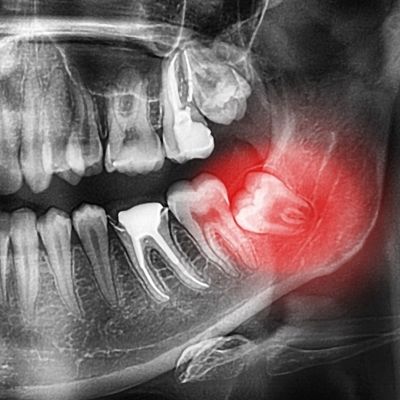

What You Should Know About Impacted Wisdom Teeth

Wisdom teeth, also known as the third set of molars located at the very back of your mouth, usually erupt during your late teen years or early adulthood (between 17-21 years old). Sometimes, these teeth do not erupt properly and may get stuck under your gum or do not have enough room to break through the gum. Dentists would consider these impacted wisdom teeth.